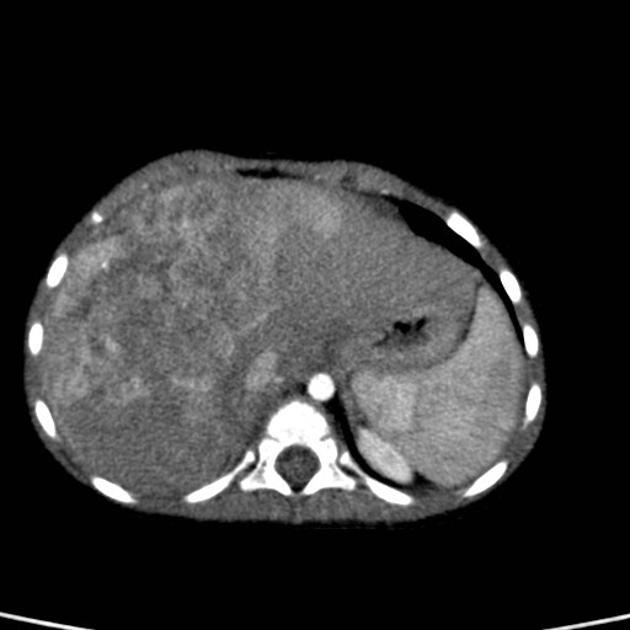

Mesenchymal hamartoma

Classically large, cystic mass w/internal septations

2nd MC benign hepatic tumor after hemangioma

AFP ^

If more solid can confuse w/hepatoblastoma